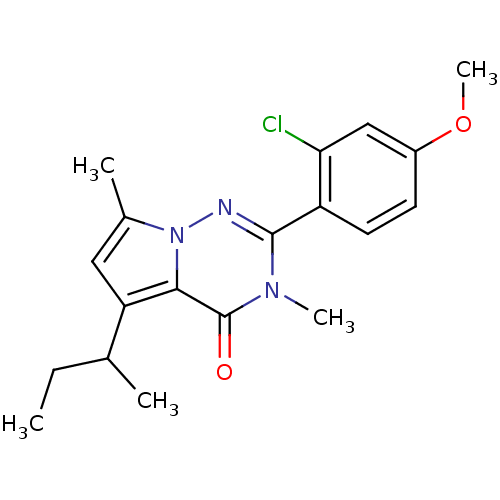

TargetCorticotropin-releasing factor receptor 1(Homo sapiens (Human))

Dupont Pharmaceuticals

Curated by ChEMBL

Dupont Pharmaceuticals

Curated by ChEMBL

Affinity DataEC50: 0.600nMAssay Description:Antagonist activity at human CRF1 receptor expressed in CHO-K1 cells assessed as CRF-stimulated cAMP accumulation by enzyme immunoassayMore data for this Ligand-Target Pair